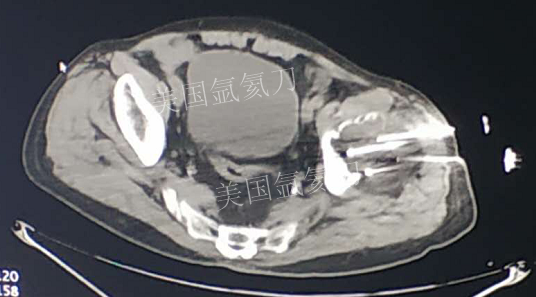

73岁臀部氩氦刀冷冻消融